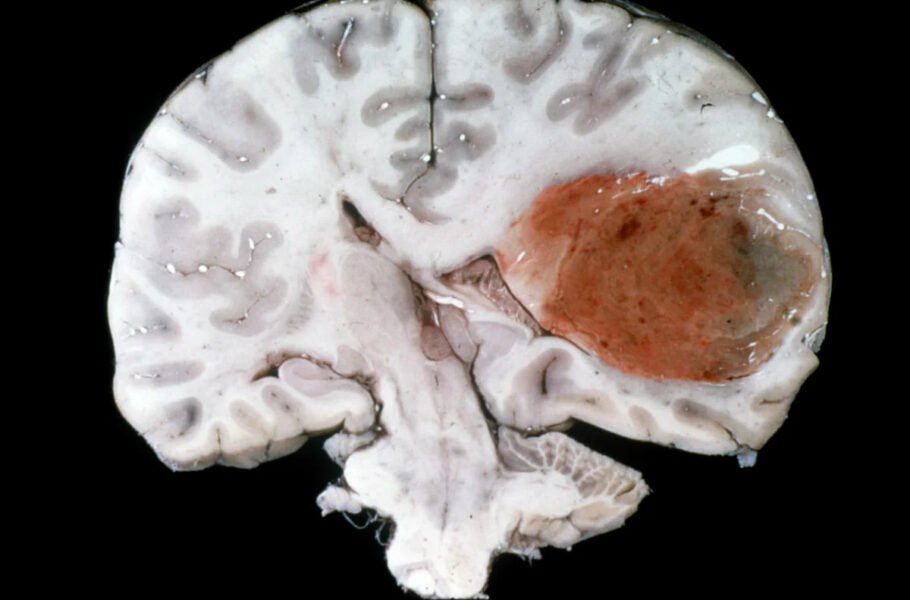

درمان جدید سرطان، اندازه یک تومور مغزی کشنده را در عرض چند روز کاهش داد

یزدفردا: این روش جدید مبتنی بر سیستم ایمنی بدن خود بیمار است و میتواند در شرایطی که سایر درمانها با شکست مواجه میشوند، موفقیتآ ...